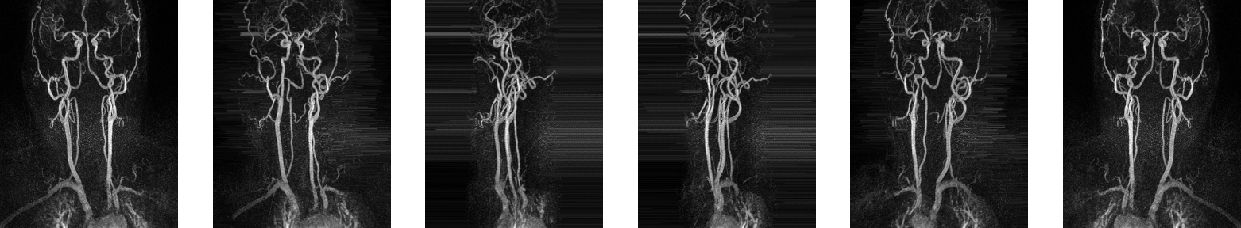

As one targeted application, we test the proposed model for segmenting blood vessels in 3D magnetic resonance angiography (MRA) scans (Fig. 1). We are given volumetric MRA scans of 119 patients provided by the Department of Neuroradiology Innsbruck 111https://www.i-med.ac.at/neuroradiologie, which face the arteries and veins between the brain and the chest. Also the 3D ground truths of these 119 patients have been provided. These segmentation masks have been generated by hand which takes hours for each patient. Our goal is the fully automated generation of sparse 3D segmentation masks of those vessels. For that purpose we use deep learning and neural networks. At the first glance, this problem may seem to be quite easy because we only have two labels (background and blood vessel), where thresholding could be applied. However, we are not interested into segmentation of those vessels with highest intensity, but in those which assist the doctor to detect dangerous to health abnormalities. This is the reason why we can not use sliding-window techniques, since the model is not able to determine out of a small patch if the seen vessel is “important” for the segmentation. Other challenges are caused by the big size of the volumes ( voxels) and by the very unbalanced distribution (in average, 99.76 % of all voxels indicate background).

As mentioned in the introduction, the main idea is to include projection layers from different directions. Due to the high sparsity and the orientation of the vessels in our application, maximum intensity projection (MIP) as projection technique seems to be an appropriate choice (Fig. 2).